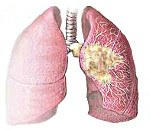

Центральный рак легкого. Злокачественная опухоль, поражающая крупные бронхи, вплоть до субсегментарных ветвей. Ранние симптомы центрального рака легкого включают кашель, кровохарканье, одышку; поздние симптомы связаны с осложнениями: обтурационной пневмонией, синдромом ВПВ, метастазами. Верификация диагноза осуществляется путем проведения рентгенографии и КТ легких, бронхоскопии с прицельной биопсией, спирометрии. В операбельных случаях лечение центрального рака легкого хирургическое, радикальное (объем резекции от лобэктомии до расширенной или комбинированной пневмонэктомии), дополненное послеоперационной лучевой терапией, химиотерапией.

Центральный рак легкого - бронхогенный рак с внутри- или перибронхиапьным ростом, исходящий из проксимальных отделов бронхиального дерева - главных, долевых или сегментарных бронхов. Это самая частая клинико-рентгенологическая форма заболевания, составляющая до 70% рака легкого (на долю периферического рака легкого приходится порядка 30%). Однако если периферический рак чаще при выявляется при профилактической флюорографии, еще до возникновения симптомов, то центральный - преимущественно в связи с появлением жалоб. Это приводит к тому, что каждый третий пациент с центральным раком легкого, самостоятельно обратившейся к врачу, оказывается уже неоперабельным.